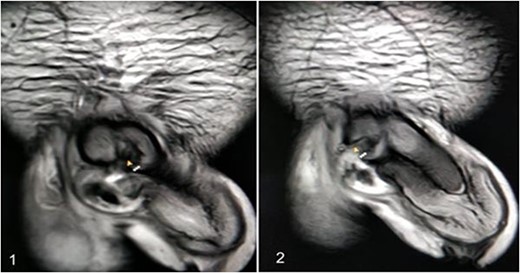

A 37-year-old male presented with a history of a ‘snap’ sound and immediate detumescence of penis during intercourse, when he fell and hit the pubic bone of his partner. There was generalized swelling and pain in the penis. There was acute retention of urine, an attempt to pass a catheter failed and the patient underwent supra-pubic catheterization. On examination, there was classical ‘eggplant deformity’ of the penis with blood at the tip of the meatus. MRI showed a tunical tear on both sides at the penoscrotal junction with indistinct urethra and extensive hematoma in the proximal penile shaft (Fig. 1). With the diagnosis of a fractured penis and possible urethral injury, after proper counselling, the patient was taken up for surgery. On the table, a retrograde urethrogram (RGU) was done showing evidence of partial urethral disruption. On exploration with penoscrotal vertical incision, there was total transection of proximal penile urethra, and a 1.5 cm tunical injury of corpus cavernosum on both sides ventrally (Fig. 2). There was extensive hematoma. Corpora sutured with 4.0 prolene after reconstructing the midline septum. Urethral ends mobilized and anastomosed with 3.0 vicryl in a single layer with minimal spatulation (Fig. 3). The patient was discharged on the 5th post-operative day; Foley catheter was removed on day 21. Follow-up RGU done after 3 months showed no evidence of stricture (Fig. 4).

Follow-up RGU done after 3 months showing no evidence of stricture.